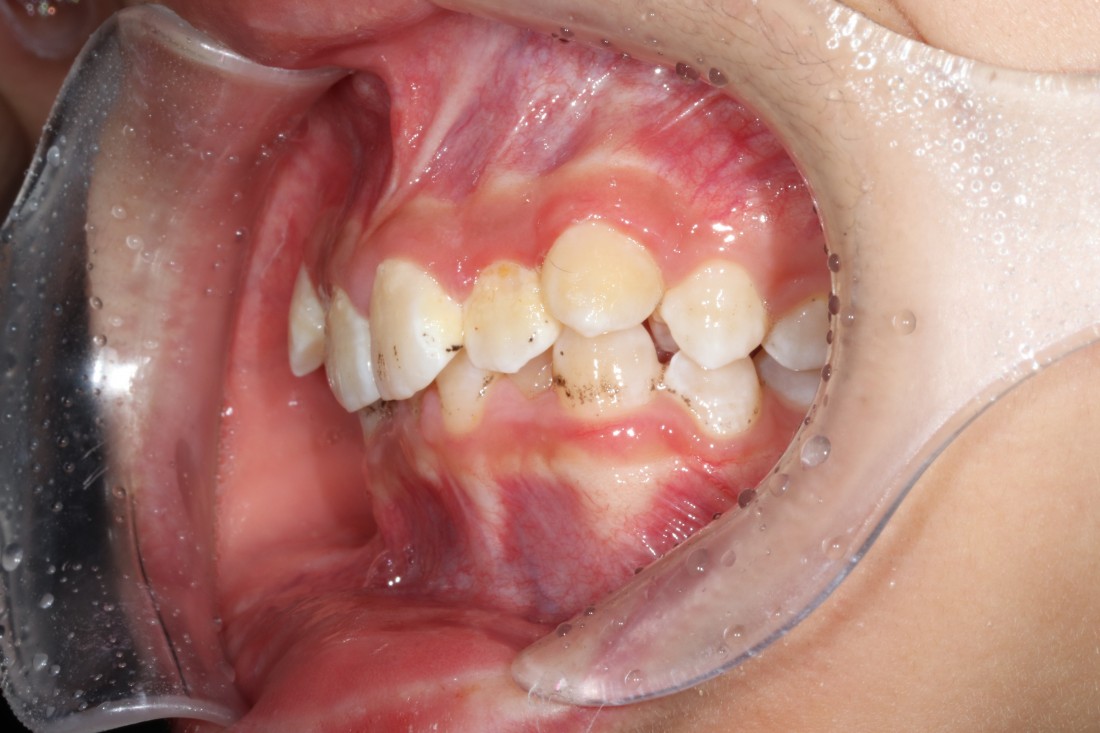

10대 청소년 학생들을 만나다보면

다른 사람들과 마주치거나 대화하는 것도

불편해하는 경우들이 보이는데요.

교정진료 역시 조용한 공간에서

프라이빗하게 받고 싶어하는

경우들이 더 많은 것 같습니다.